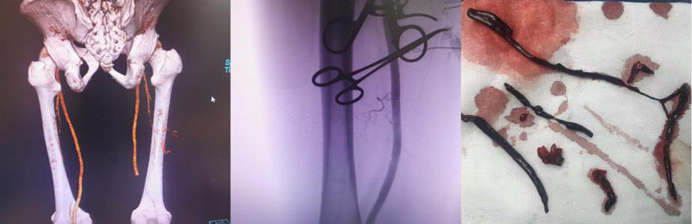

血管疾病專(zhuan) 業(ye) 組:常規開展主動脈夾層的腔內(nei) 手術、胸主動脈瘤、腹主動脈瘤的腔內(nei) 手術和開放手術、頸動脈內(nei) 膜剝脫和支架置入手術、肝硬化、門靜脈高壓症斷流、脾腎靜脈及門腔靜脈分流、下肢動脈閉塞症、深靜脈血栓形成、糖尿病足、血栓閉塞性脈管炎、動脈栓塞等疾病的外科血管旁路搭橋,血管成型,靜脈動脈化,球囊導管取栓,腔靜脈濾器植入,腸係膜靜脈血栓形成經股動脈穿刺腸係膜上動脈持續溶栓治療,大、小隱靜脈曲張微創手術,下腔靜脈、股動脈等血管損傷(shang) 的救治。並成功開展目前最前沿的高難度主動脈弓三開窗腹膜分支支架置入術。

下肢動脈閉塞切開取栓術